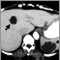

Polycystic kidney disease is a kidney disorder passed down through families in which multiple cysts form on the kidneys, causing them to become enlarged.

Persons with PKD have multiple clusters of cysts form on the kidneys. The exact action that triggers cyst formation is unknown. In early stages of the disease, the cysts cause the kidney to swell, disrupting kidney function and leading to chronic high blood pressure and kidney infections. The cysts may cause the kidneys to increase production of erythropoietin, a hormone that stimulates production of red blood cells. This leads to too many red blood cells, rather than the anemia seen in chronic kidney disease.

Polycystic kidney disease and associated cysts on the liver or other organs may be detected with the following tests: